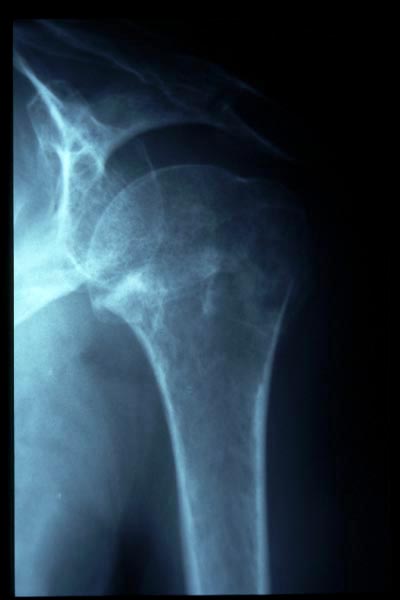

Fractura impactada de húmero .

Fractura compleja de húmero.